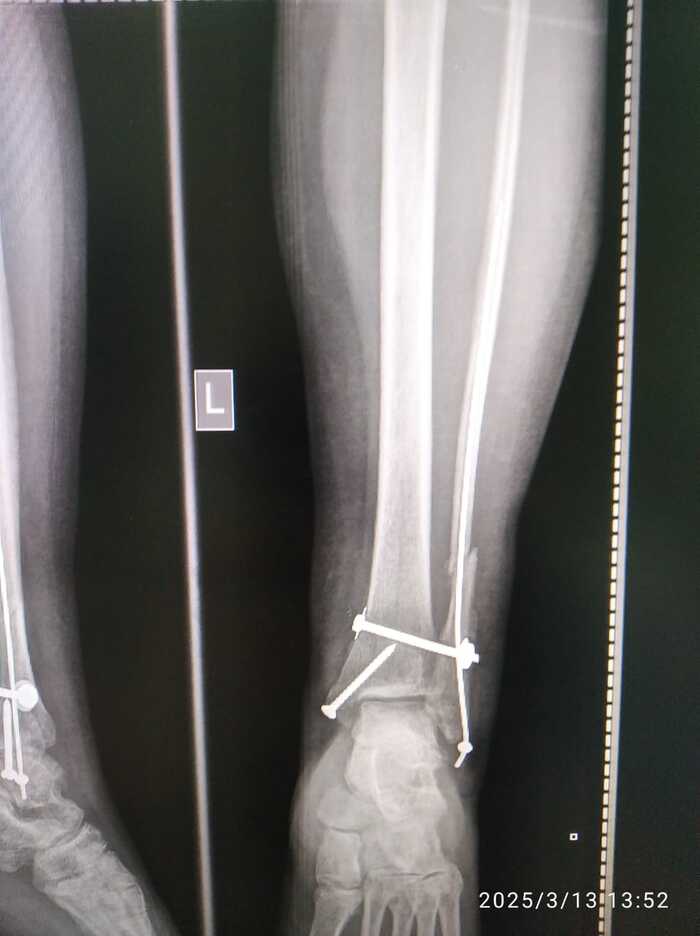

Мама сломала ногу 19 ноября 2024 года. Неудачно упала с дивана - перелом в трёх местах со смещением и разрывом связок. Ниже снимки сразу после операции

Поставили такие спицы. Прощу прощения, я не врач и могу неправильно употреблять некоторые термины.

Ниже прилагаю сегодняшние снимки.